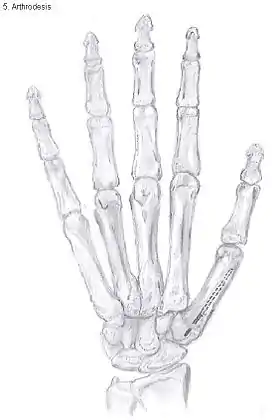

Arthrodesis

Arthrodesis of the CMC1 joint is a surgical procedure in which the trapezium bone and the metacarpal bone of the thumb are secured together. Because the joint is fixed, and therefore can not be moved, the complaints of the patient are mainly gone.

During the surgery the two bones will be fixated using K-wires. The use of plates and screws has also been described. The thumb will be positioned in a way it can still perform a pinch grip. Because of the fixation, the two bones will fuse together. This will occur usually within four to six weeks.

However, this technique has some disadvantages.[31] The palm of the hand is unable to be flattened, making it difficult to wear gloves or put your hand in a pocket. Because the stress on the CMC1 joint is now divided over the other joints, those joints are more likely to be damaged.[37]

Nevertheless, this procedure can be used in patients with stage II and III CMC OA as well as in young people with posttraumatic OA.[31]